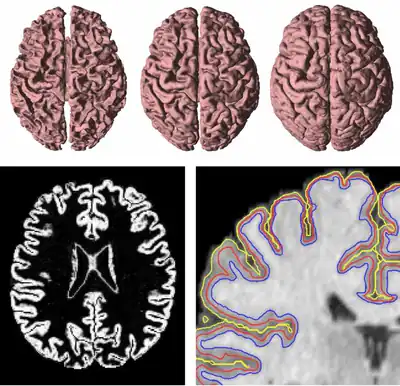

GVF has been used to find both inner, central, and central cortical surfaces in the analysis of brain images,[5] as shown in Figure 4. The process first finds the inner surface using a three-dimensional geometric deformable model with conventional forces. Then the central surface is found by exploiting the central tendency property of GVF. In particular, the cortical membership function of the human brain cortex, derived using a fuzzy classifier, is used to compute GVF as if itself were a thick edge map. The computed GVF vectors point towards the center of the cortex and can then be used as external forces to drive the inner surface to the central surface. Finally, another geometric deformable model with conventional forces is used to drive the central surface to a position on the outer surface of the cortex.